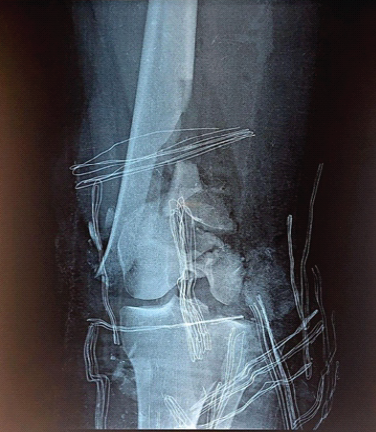

Cedell’s Fracture of the Talus Managed with Herbert Screw Fixation through Posteromedial Approach – A Case Report

Rajath S. Shetty , Shubham Y. Dakhode , Jaideep Das , Ajit S. Rathod , Aakash N. Varma , Abhishek M. Ganacharya

………………………………p.66-69